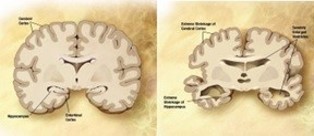

Symptoms of AD affecting the CNS

Alzheimer’s starts in the central nervous system and pro- gresses slowly from there. AD is characterized by decreasing ar- eas of the brain, damage to tissue cells, and the breakdown of neuronal connection links [18]. Tangles and amyloid plaques ac- cumulated in the brain are also thought to be a characteristic of AD. Studies of brain metabolism using MRI and PET, along with other imaging modalities, have revealed distinctive alterations in AD patients [3]. Figure 1 displays an MRI of a brain affected by AD and a normal brain [1]. Artificial intelligence has a significant role in the diagnosis of AD.